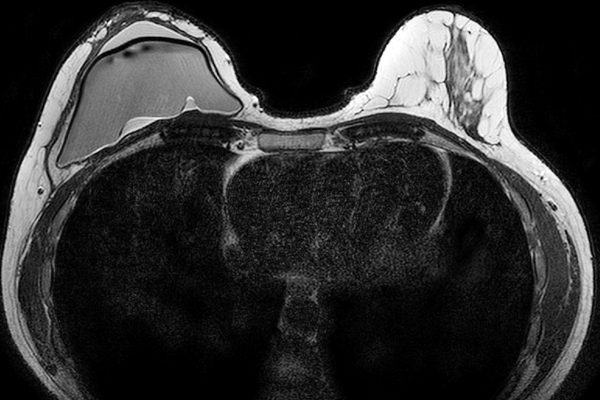

O linfoma anaplásico de grandes células associado aos implantes mamários é um linfoma T CD30 positivo raro, cuja incidência tem aumen...